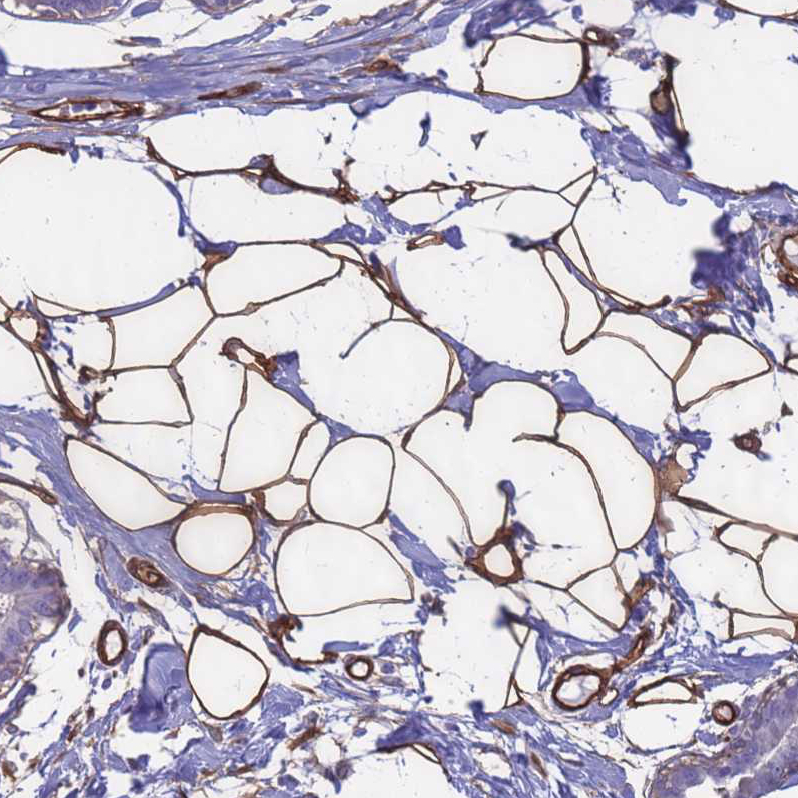

Immunohistochemical staining of human Breast shows strong membranous positivity in adipocytes.